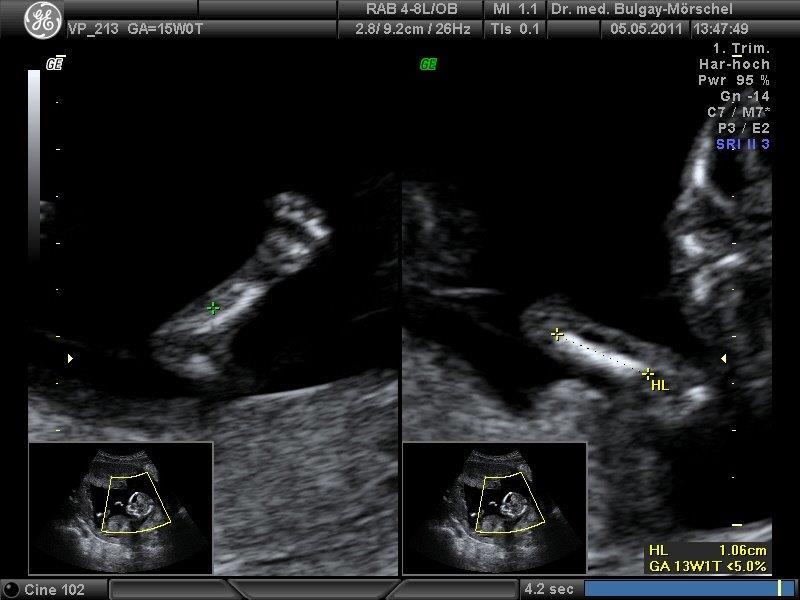

Das Ersttrimesterscreening setzt sich aus der Ultraschalluntersuchung des Kindes und einer Blutentnahme von der Mutter zusammen. Die Ultraschalluntersuchung wird zwischen der 11+0-13+6 SSW durchgeführt. Dabei wird die sog. Nackentransparenz (Nackenhautdicke) des Kindes gemessen. Aus mütterlichem Blut werden 2 Schwangerschaftshormone bestimmt. Aus diesen Werten wird ein individuelles statistisches Risiko für die T21/13 und T18 berechnet. Nähere Informationen erhalten sie unter http://www.fmf-deutschland.info/de oder